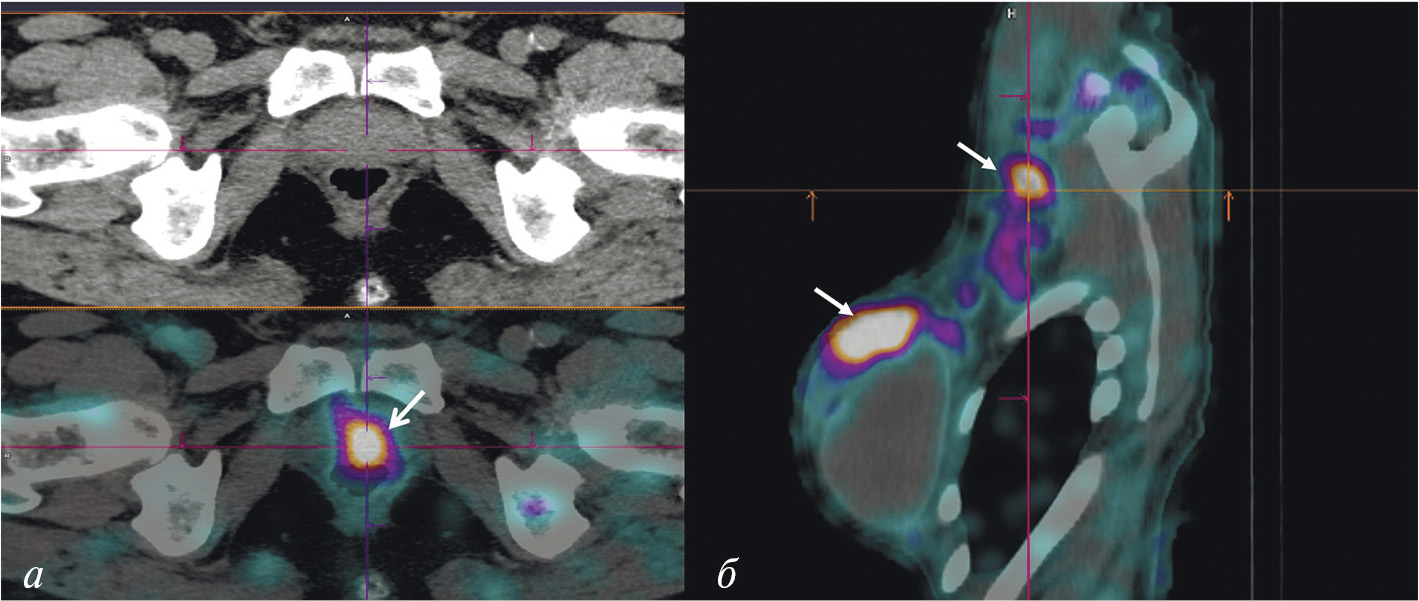

В НИИ онкологии Томского НИМЦ завершены первые фазы клинических исследований нескольких меченных технецием-99м каркасных белков (DARPin, ADAPT, Affibody), обладающих высокой аффинностью к рецептору эпидермального фактора роста второго типа (HER2/neu). Все препараты показали хорошую эффективность определения гиперэкспрессии рецептора HER2/neu при раке молочной железы и стадировании заболевания (рис. 1) [10, 11]. Кроме того, установлена возможность проведения ОФЭКТ/КТ с препаратами на базе скаффолдов для оценки эффекта терапии (рис. 2). Помимо основы РФЛП для диагностики злокачественных новообразований, каркасные белки могут служить вектором доставки при создании таргетных соединений для лечения злокачественных новообразований с гиперэкспрессией рецептора HER2/neu [13].

Рис. 1. ПЭТ-изображение пациентки с HER2/neu-позитивным раком молочной железы, выполненное через 5 суток после введения 89Zr-транстузумаба (a), стрелками обозначены метастазы в печень и кости [12]; ОФЭКТ-изображение пациентки с HER2/neu-позитивным раком молочной железы через 2 ч после введения 99mTc-ADAPT6 (б), стрелками обозначены первичная опухоль, метастазы в лимфатические узлы, печень и кости

Рис. 2. ОФЭКТ/КТ-изображение пациентки с HER2/neu-позитивным раком правой молочной железы до начала лечения, выполненное через 2 ч после введения 99mTc-DARPIN-G3 (а), стрелками обозначены первичная опухоль (SUVmax = 3.1), метастазы в лимфатические узлы (SUVmax = 8.8) и кости; ОФЭКТ/КТ-изображение той же пациентки после двух курсов терапии транстузумабом через 2 ч после введения 99mTc-DARPIN-G3 (б), стрелками обозначена первичная опухоль (SUVmax = 0.55), метастазы не визуализируются